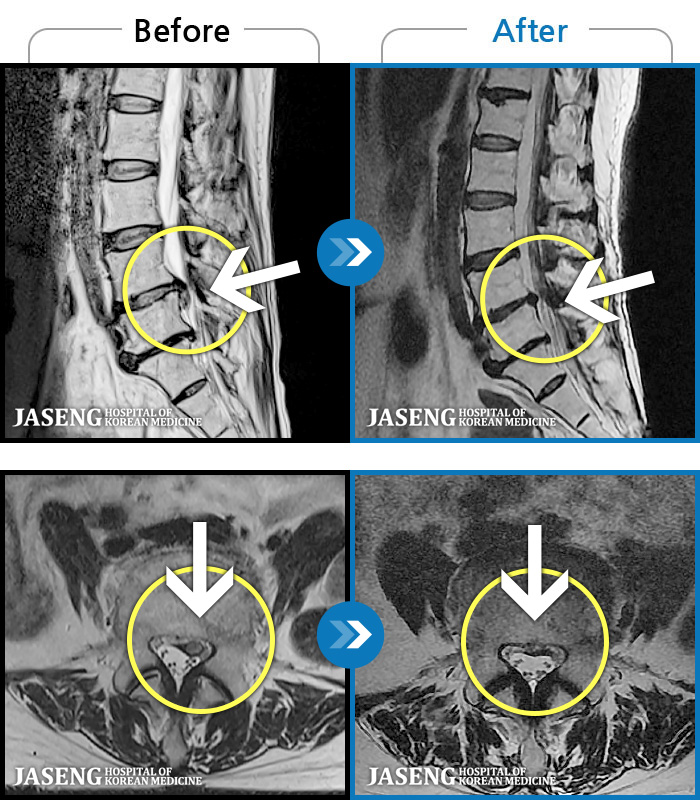

1,293 MRI ũ ʸ Ȯϼ.